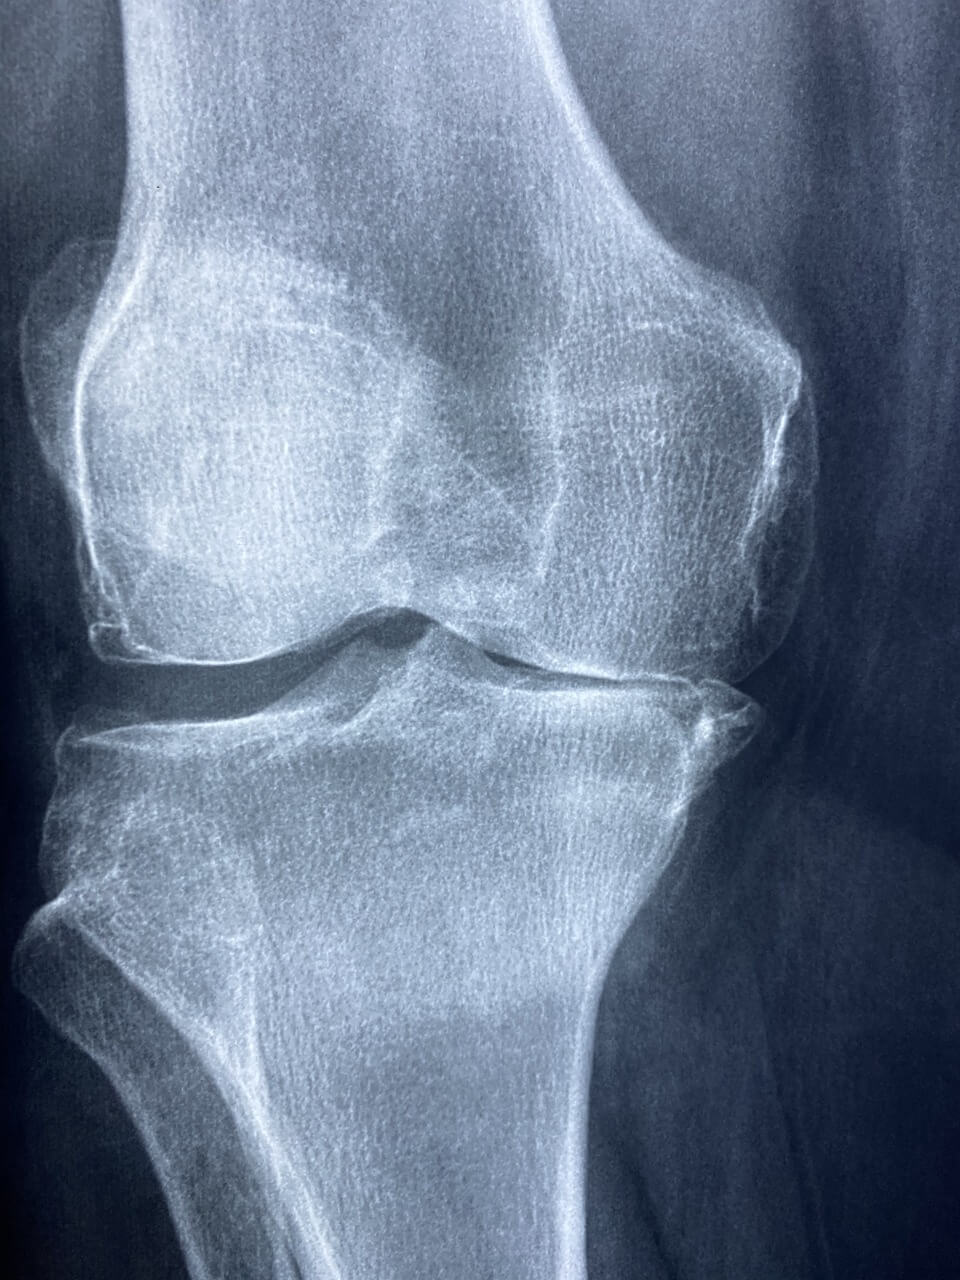

관절염은 관절에 염증이 생기는 질환으로, 주로 통증, 부기, 뻣뻣함 등의 증상을 동반합니다. 관절염은 크게 퇴행성 관절염과 류마티스 관절염으로 나눌 수 있습니다. 퇴행성 관절염은 나이가 들면서 관절의 연골이 닳아 없어지는 현상으로 발생하며, 류마티스 관절염은 면역체계의 이상으로 인해 발생하는 자가면역 질환입니다.

관절염 초기증상 관리 및 치료 방법

관절염 초기 증상을 관리하기 위해서는 다음과 같은 방법들이 있습니다.

- 약물 치료 : 비스테로이드 항염증제(NSAIDs)나 진통제를 사용하여 통증을 완화할 수 있습니다.

- 물리치료 : 전문 물리치료사의 도움을 받아 관절의 움직임을 개선하고 통증을 줄일 수 있습니다.